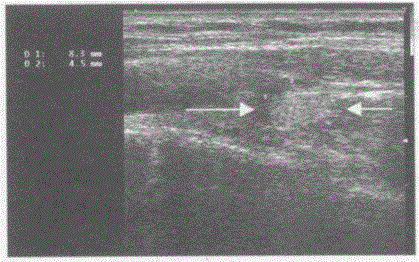

问题 临床资料:女,47岁,自诉右乳癌术后2年,感觉右颈部不适。 超声综合描述:右侧颈总动脉外侧可见0.8cm×0.4cm椭圆形增强回声区(箭头所示),内回声不均,与周围组织粘连,用探头推压,位置无变化。 超声提示:

选项 A.右侧甲状旁腺腺瘤 B.正常右侧甲状旁腺声像图 C.甲状腺右叶结节 D.右侧颈总动脉旁肿大淋巴结(右颈部淋巴结转移瘤)

答案 D